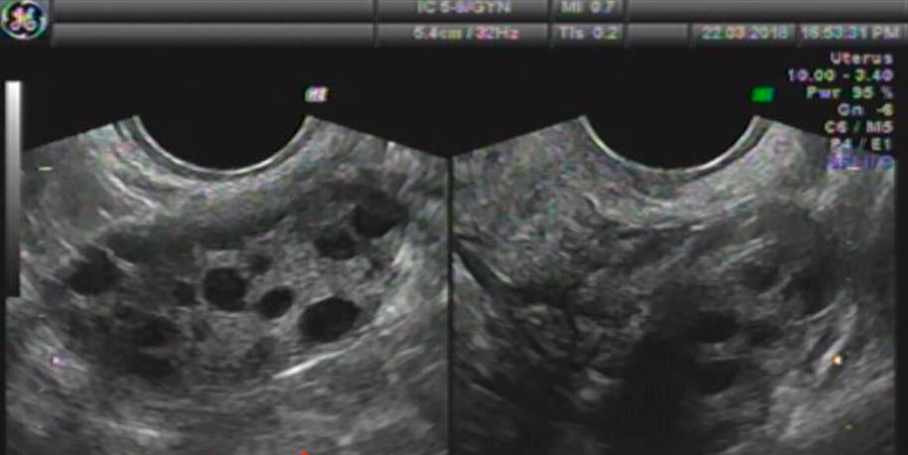

Bác sĩ chuyên khoa 2 Diêm Thị Thanh Thủy, Trưởng khoa Khám sản tự nguyện, Bệnh viện Phụ sản Hà Nội, cho biết gần đây rất nhiều bé gái tuổi dậy thì bị buồng trứng đa nang đến viện thăm khám. Trước đây, hội chứng thường xảy ra ở người lớn, là nguyên nhân gây vô sinh phổ biến với phụ nữ trẻ.

Đây là hiện tượng buồng trứng có rất nhiều nang nhỏ, các nang này không trưởng thành, không vỡ, trứng không rụng nên trẻ không có kinh nguyệt. Đây là bệnh chuyển hóa toàn thân nhưng lại thể hiện ở buồng trứng.

Dấu hiệu trẻ bị buồng trứng đa nang

Vô kinh, mất kinh, rối loạn kinh nguyệt là dấu hiệu đầu tiên, quan trọng nhất của buồng trứng đa nang. Thông thường, với trẻ đã có kinh nguyệt lần 1, sau 2 năm, chu kỳ kinh nguyệt sẽ ổn định.

Tuy nhiên, nếu sau 2 năm từ kỳ kinh đầu tiên, chu kỳ của trẻ không đều, mất kinh trong 4 tháng, cần được thăm khám ngay. Ngoài ra, khi thấy con đã dậy thì, ngực và hệ thống lông phát triển, mặt có trứng cá, nhưng một năm không có kinh nguyệt, cha mẹ cần đưa con đi khám sản phụ khoa.